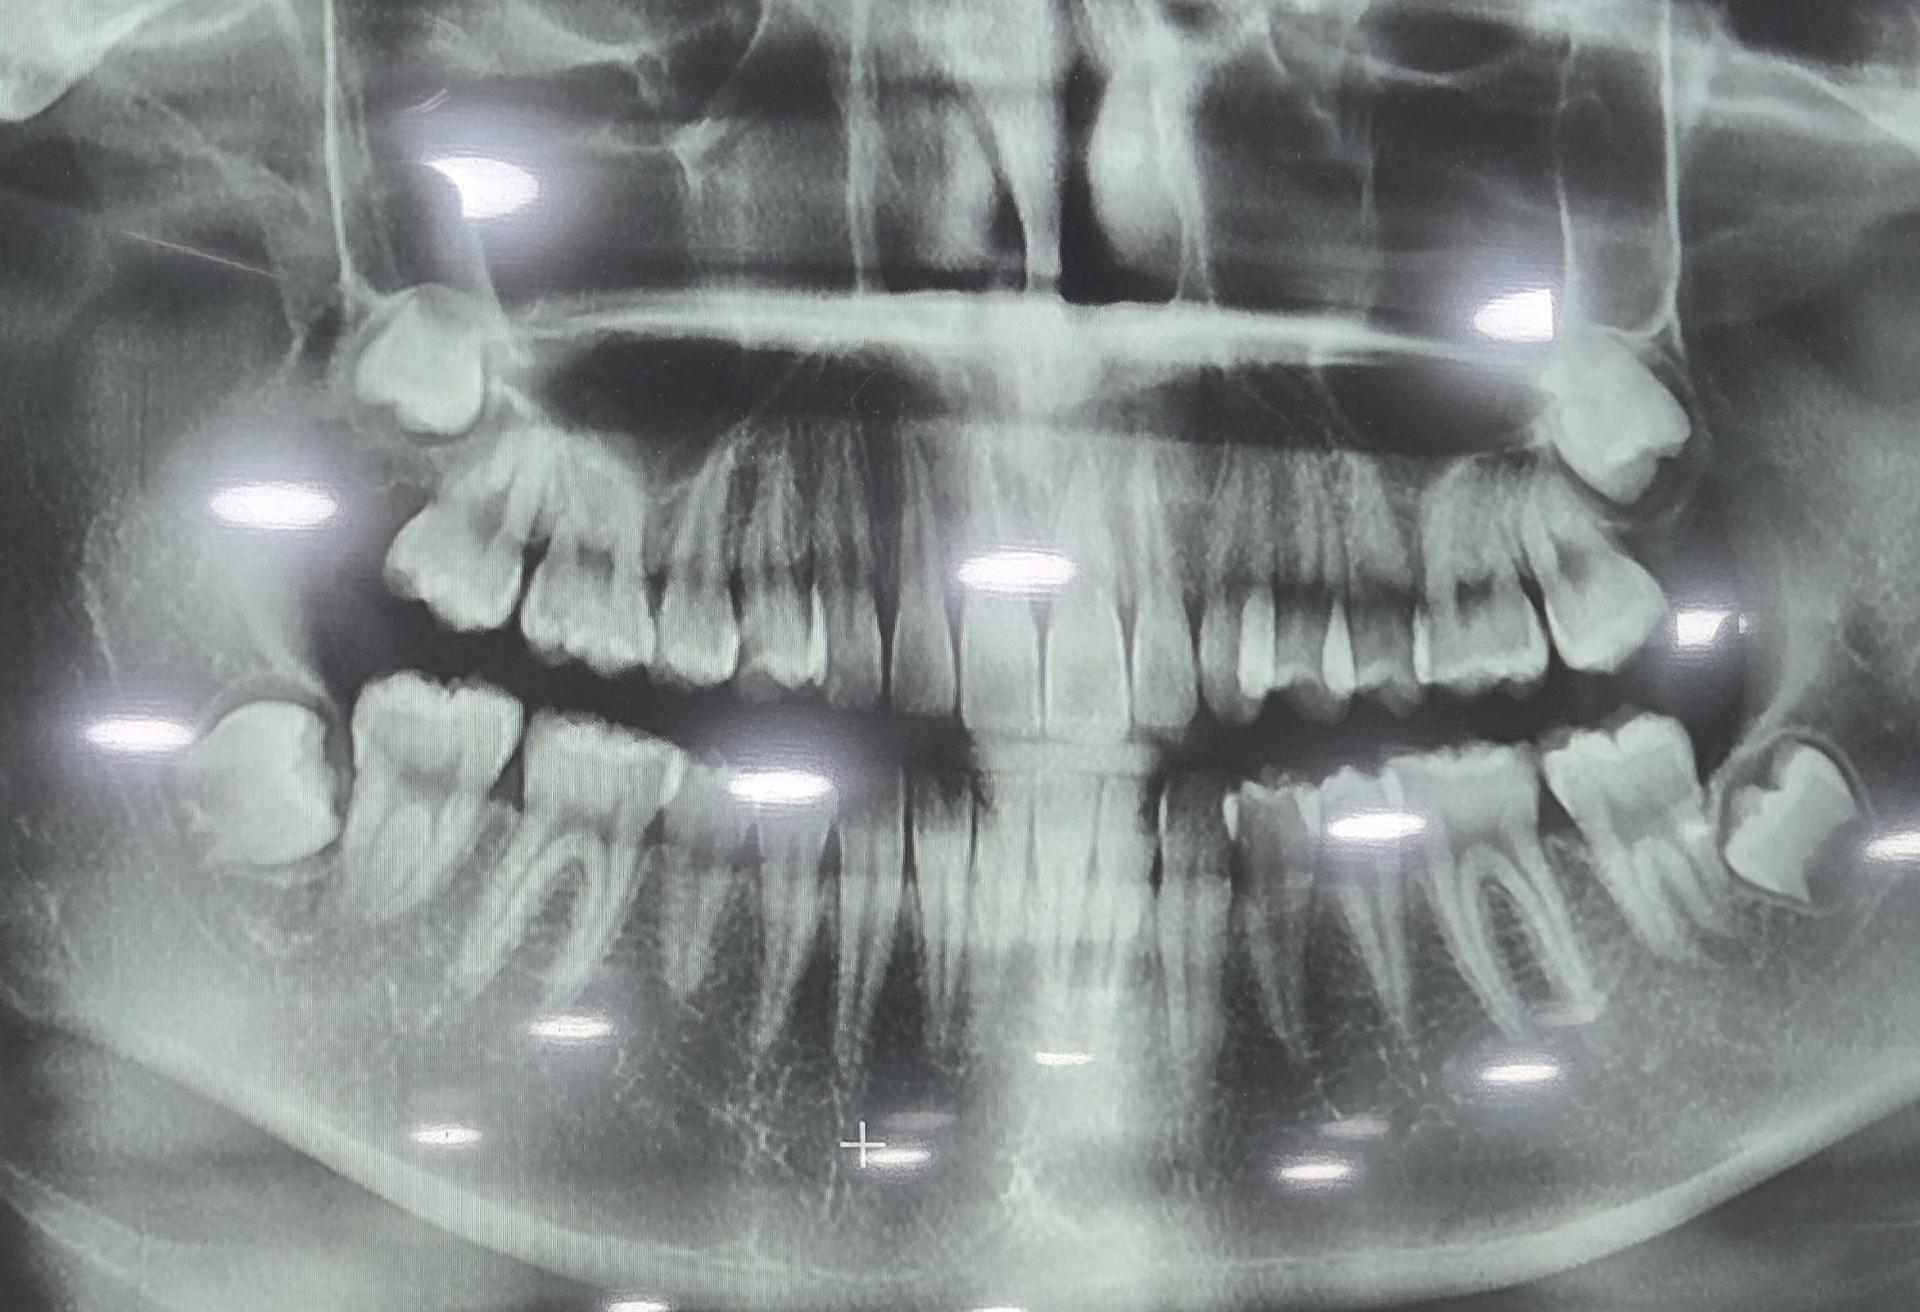

제가 10월에 어금니 통증도 있고 아래 쪽 끝 어금니 부분에 잇몸이 달랑거여서 병원에 방문하였고 X-레이를 찍었는데 사랑니가 다 있지만 괜챃다고 자라나고 있다고 하더라구요 또한 위쪽 왼쪽 어금니 통증이 있긴했지만 그때는 많이 아프지도 않고 가끔 아픈 거라 그런가보다 하고 넘겼는데 현재 위쪽 왼쪽 어금니 통증이 심해요ㅠ 끝 어금니와 옆에 있는 어금니 사이가 혓바닥으로만 해도 아프고 왼쪽 끝 어금니 부분에 있는 잇몸 끝을 혓바닥으로 만져보면 어금니 치아모양이 느껴집니다. 하지만 제가 봤을 때 잇몸의 더 이상의 자리가 없고 자라나더라도 옆으로 자라나거나 볼을 씹을 거 같은데 계속 자라나게 둬도 괜찮은 건가요? 그리고 잇몸 부분이 반대쪽에 비해 부어있어요!

사랑니가 맹출하면서 불편감이 생길수도 잇을것같습니다. 잇몸치료를 해보시고 계속해서 불편하시면 사랑니 발치를 하시는게 좋을것같습니다.